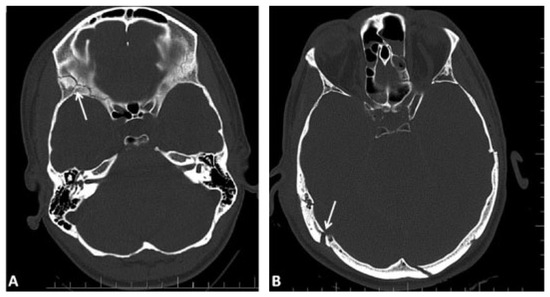

Fractures of the walls of the paranasal sinuses with the presence or the absence of opacification of the paranasal sinuses on CT imaging (i.e., blood or other fluids) are also documented. Illustrative examples are presented in Figure 3 and Figure 4A.

Figure 3. Examples of fractures and definitions. (A) Depressed fracture (displaced toward the brain) of the parietal bone. (B) Multiple fractures, depressed on the right frontal bone, displaced on the left frontal bone, with involvement and opacification of the frontal sinus bilaterally. (C) Transverse fracture line through the right petrous bone, another fracture line through the right apex petrosis, opacification of the left mastoid with fracture at the rostral rim. (D) Transverse maximum intensity projection (MIP) – reconstruction of the skull base with fragmented fracture of the right middle skull base fossa. (E): Nonfragmented fracture of the left parietal bone. (F) Curved MIP—reconstruction of the occipital bones with fragmented fracture, displaced but not depressed.